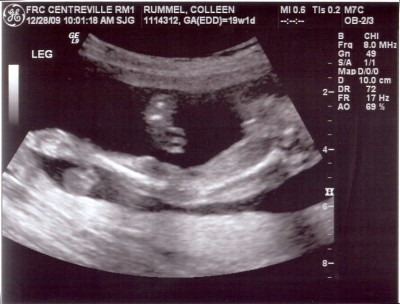

So cute! I love sonogram pics.